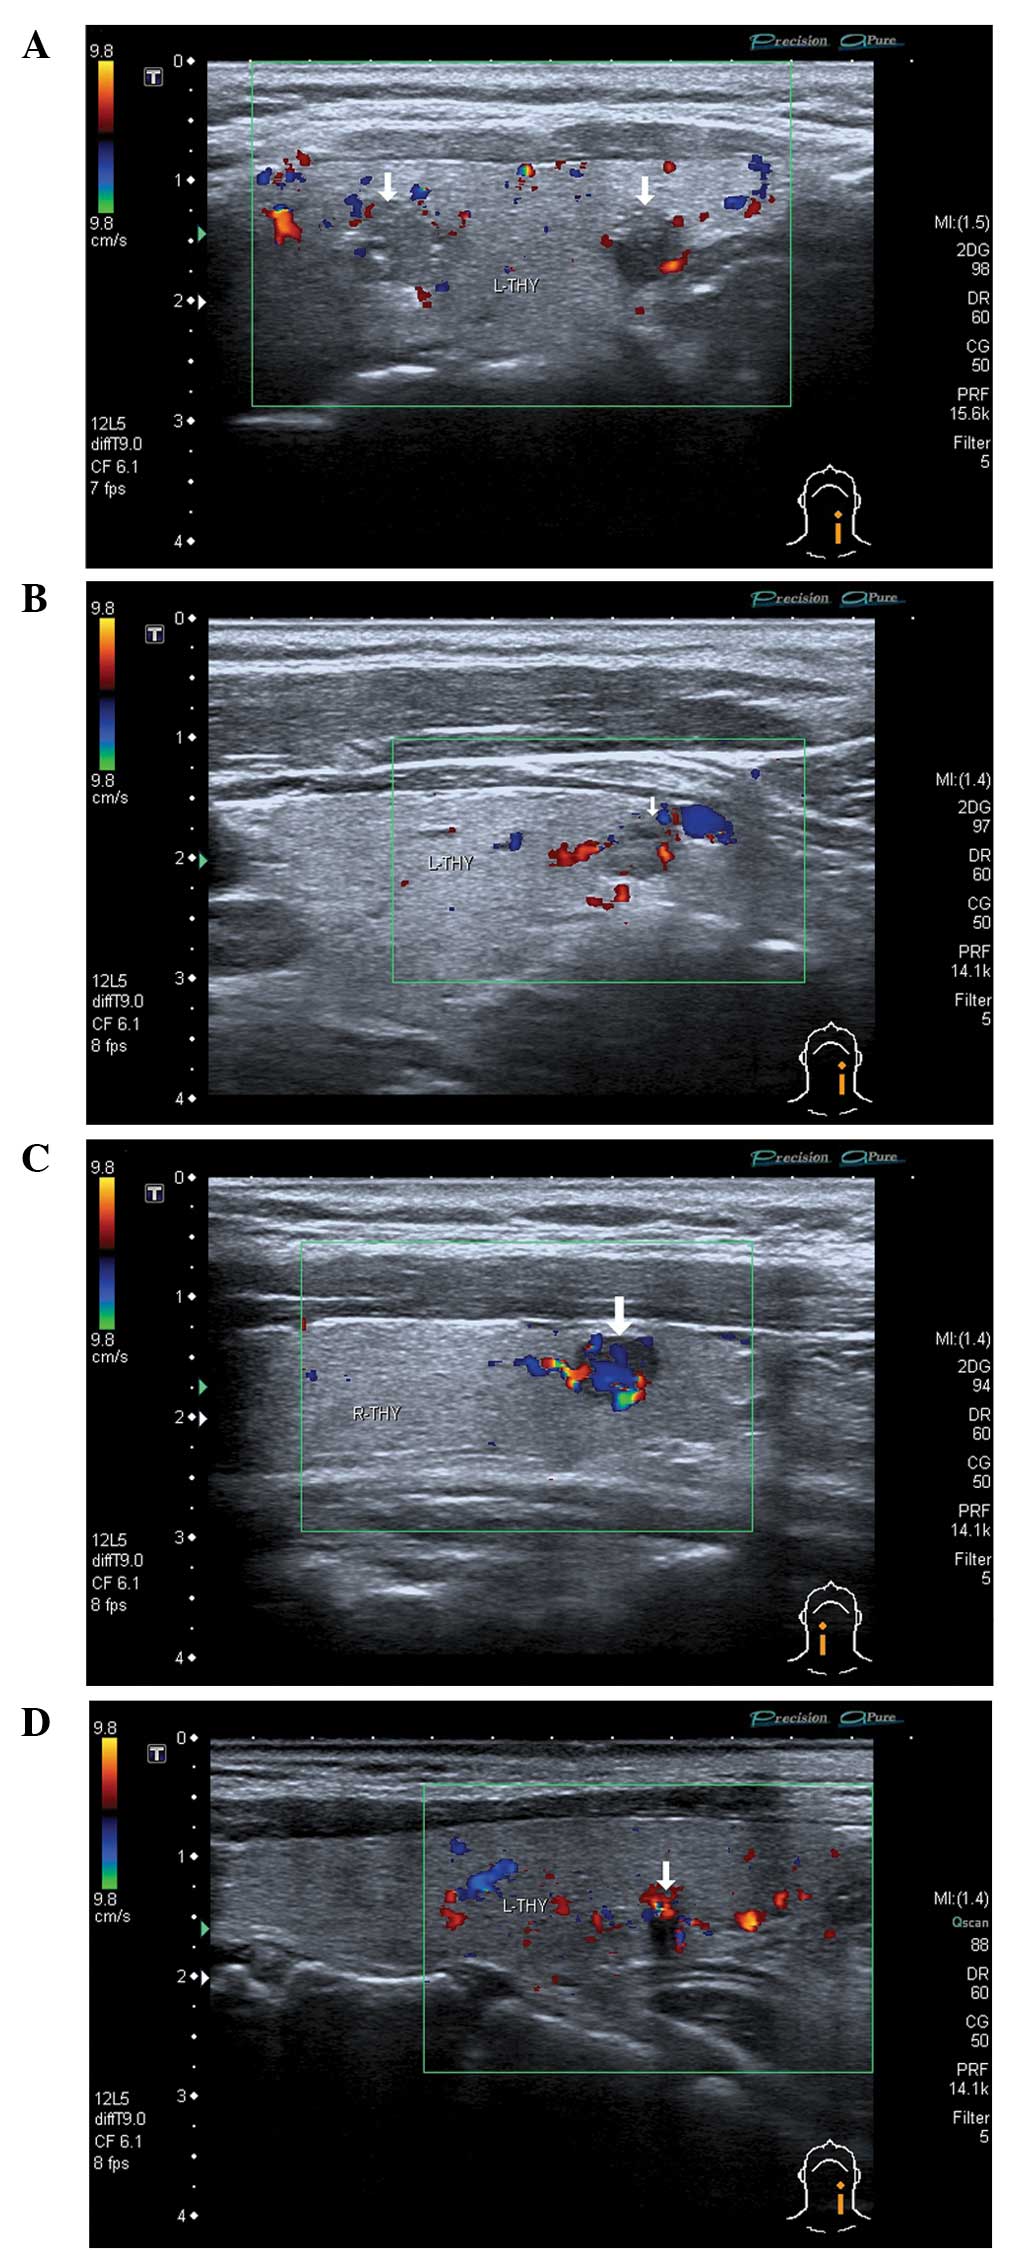

Thyroid cancer affects your thyroid gland which is a butterfly-shaped organ in your neck. Several reports have proposed that increased vascular flow on color Doppler sonography may be associated with malignancy in thyroid nodules. A malignant thyroid nodule tends to have ill-defined margins on ultrasound Fig.

Incredible Thyroid Nodule Thyroid Cancer Ultrasound Colors Ideas. Color on your thyroid ultrasound means that color doppler was applied and blood flow was detected. In A the two-part figure on the left shows a thyroid adenoma with a peripheral halo.

Papillary Thyroid Carcinoma A Color Doppler Ultrasound Showing Download Scientific Diagram

Colour Doppler Image Of Malignant Thyroid Nodule Show Increased And Download Scientific Diagram

Role Of Color Doppler Us A Transverse Gray Scale Image Of Download Scientific Diagram